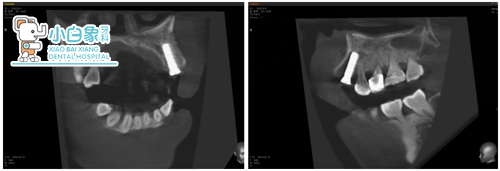

治疗过程:23必兰局麻下切开翻瓣,拔除残根,根尖区骨缺损,根尖大量肉芽组织,彻底去除后24根面部分暴露,预备种植窝后植入ITI3.3*12mm骨水平种植体一枚,上愈合帽后填塞Bio-oss骨粉,海奥膜覆盖,严密缝合。

植入后X线片